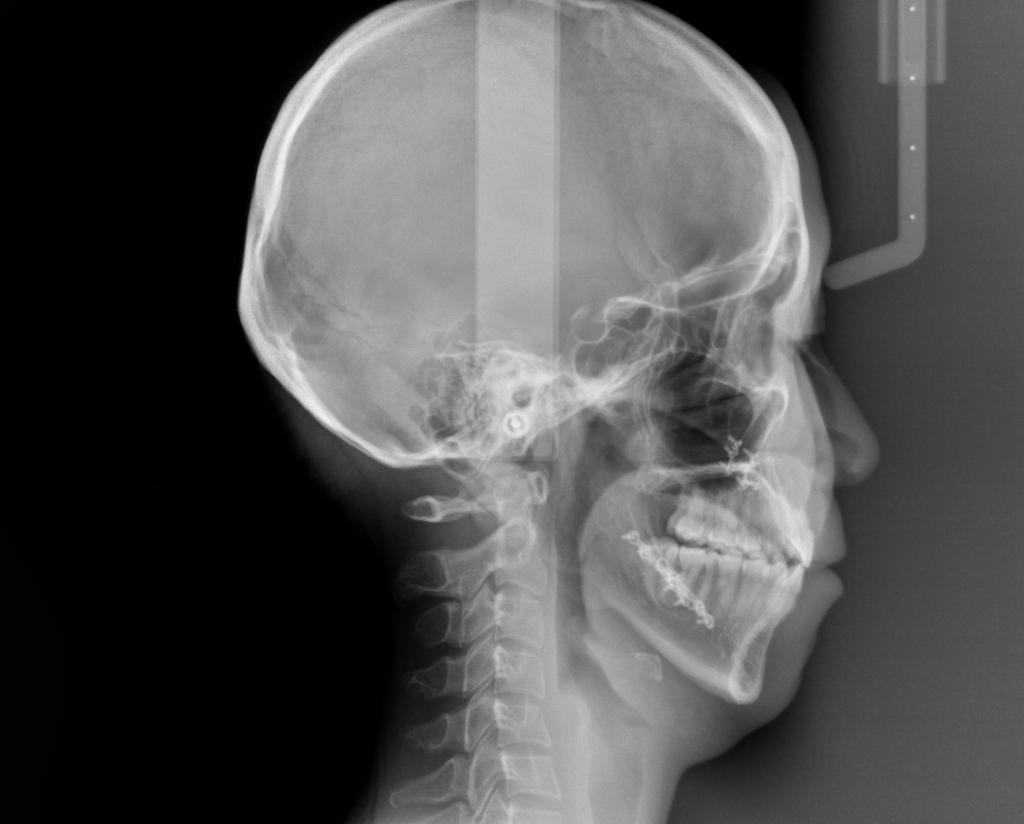

- 顎、顔の歪みの矯正治療

- 息がし難い

- 下顎前突(受け口)の方は、まれに治療中・治療後に下アゴが平均を著しく上回って成長することがあります。その場合、成人になって下アゴを後退させる手術が必要になる可能性があります。

- アゴが横にずれている場合(骨格性のタイプ)は、手術を伴う矯正治療以外では顔のゆがみは治せません。